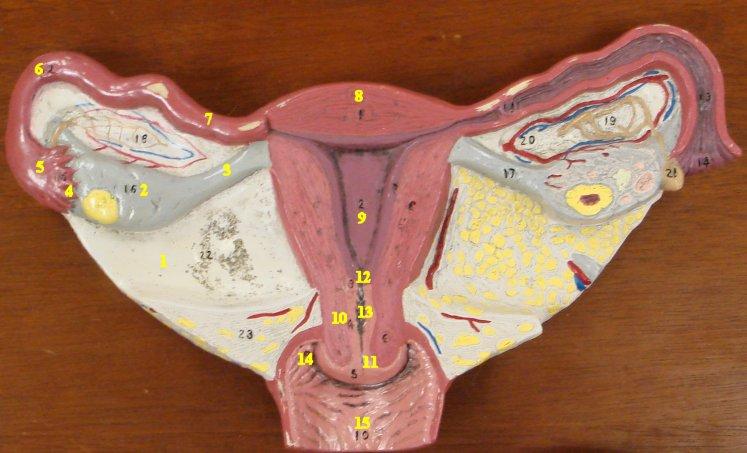

Broad ligament

Cervix

Corpus luteum

Endometrium

Fimbriae

7 & 18

Mature (=Graafian, = antral) follicle

Myometrium

Overian ligament

Ovary

Perimetrium

Primordial/primary/secondary follicle

Round ligament (of uterus)

Uterine (=fallopian) tube

Uterus

Vagina